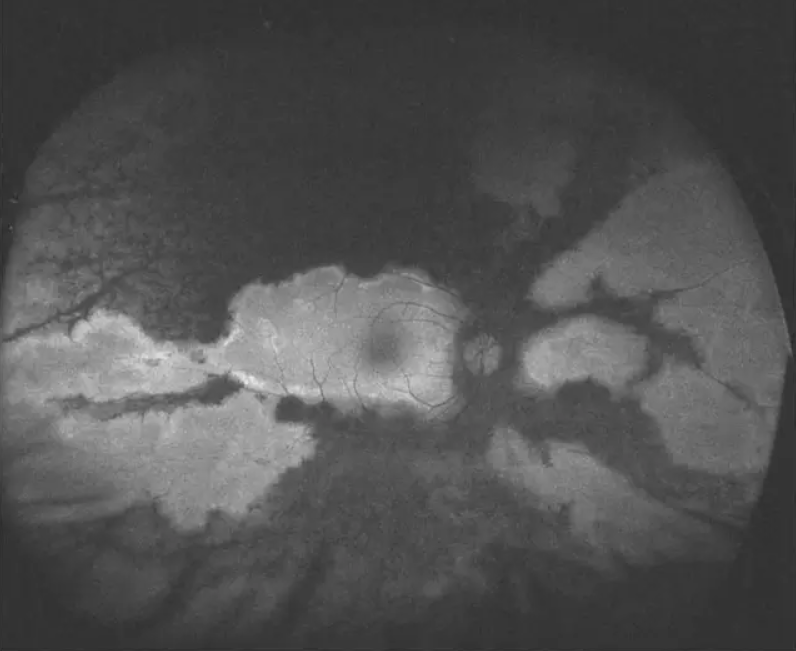

▲AFC-210超广角眼底彩照,在免散瞳情况下即可拍摄,患者无需散瞳,瞳孔直径大于2mm即可检查。

▲AFC-210超广角自发荧光。同样是在免散瞳的情况下即可进行拍摄,使用绿激光进行激发,对黄斑的伤害更小。